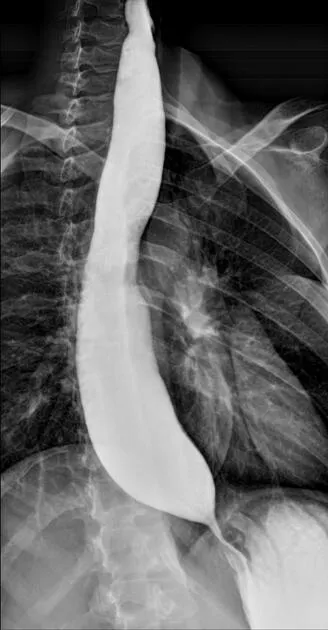

- Barium Swallow (Esophagus):

- Assesses dysphagia, odynophagia, GERD, motility disorders (e.g., achalasia).

- Identifies: Strictures, webs, diverticula (Zenker's: posterior pharyngoesophageal outpouching), masses, hiatus hernia.

⭐ Bird's beak sign on barium swallow is characteristic of achalasia cardia.

- Esophageal cancer: Presents as apple-core lesion or irregular, ulcerated filling defect.